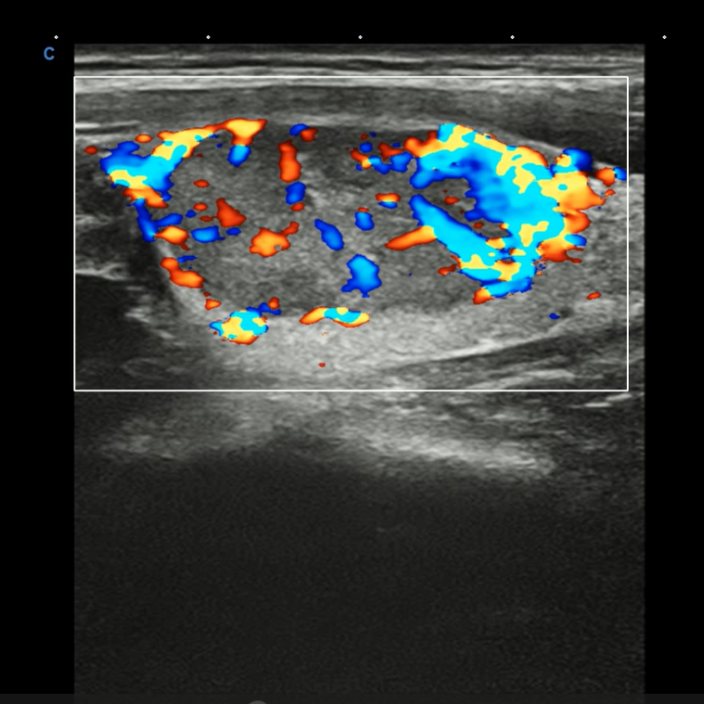

甲状腺结节中血流图像